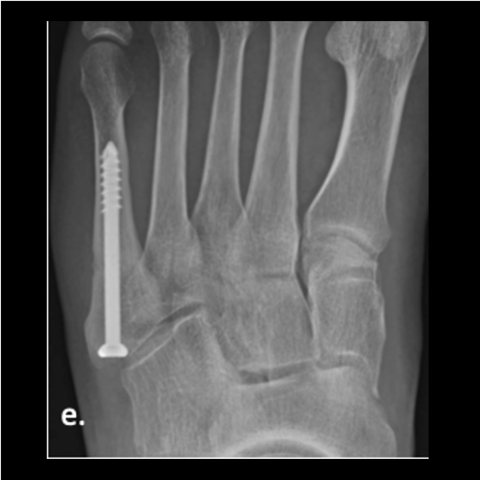

Figure 4e

Figure 4e. The 24-year-old soldier jumped off the back of a truck, refracturing his metatarsal. Here is the foot a year post-surgery after jumping off the truck.